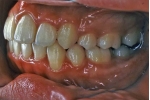

マルチブラケット終了時